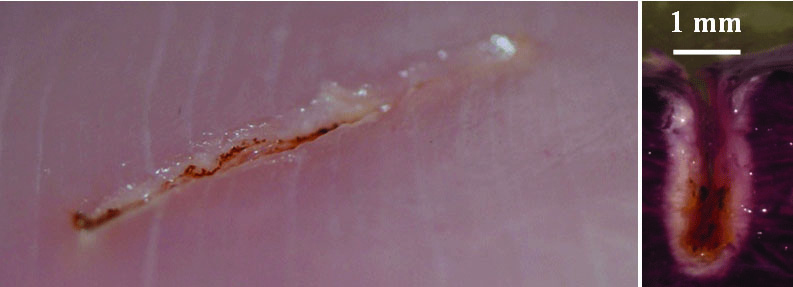

The images shown in Figure 7 and Figure 8 represent a series of photos (top row) and histology (bottom row) of soft-tissue cutting at five different speeds of movement, ranging from 12.5 mm per second to 0 mm per second (stop for several seconds) performed with a traditional diode laser using fixed power (Figure 7) and TOP surgery with automatic power control (Figure 8).13 These experiments were performed using a translation stage with programmable speed and controlled vertical force between the fiber and the sample. To visualize tissue damage, nitro blue tetrazolium chloride (NBTC) viability staining was used, so stained areas show live cells, while cells in white areas are dead. This stain became a standard tool to visualize tissue thermal damage in laser surgery.16,17 It is characteristic that when the speed decreases, the cutting depth and level of collateral tissue damage and carbonization increase sharply for diode lasers, but they remain essentially the same with the new laser technology. The histological evaluations (Figure 7 and Figure 8) illustrate how the influence of cutting speed can reduce tissue damage with automated power control.

Fig 8. NBTC stain showing effect of cutting speed on collateral thermal damage using

TOP surgery cuts.

Figure 8